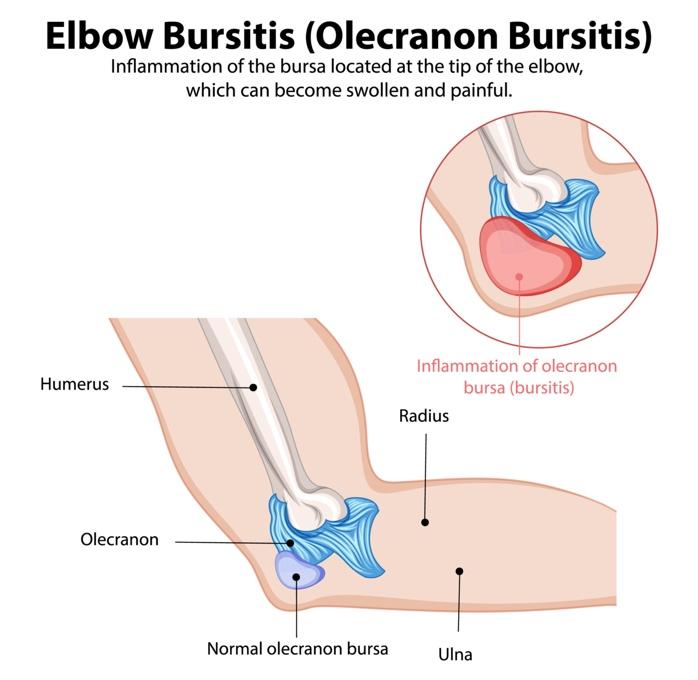

Elbow bursitis, also known as olecranon bursitis, could be the reason. This condition occurs when the small, fluid-filled sac (bursa) at the back of your elbow becomes inflamed. While it’s often mild, elbow bursitis can lead to noticeable swelling, discomfort, and even pain, making it difficult to perform everyday activities. Let’s explore what causes this condition, how to recognize its symptoms, and what you can do to manage it effectively.

Elbow bursitis, also known as olecranon bursitis, is an inflammation of the bursa located just behind the bony tip of the elbow (olecranon). The bursa is a fluid-filled sac that allows the elbow to move smoothly without friction. When inflamed, it can lead to noticeable swelling and discomfort.

Anatomy of the Elbow

If you bend your arm and touch your elbow, the bony point you feel at the tip of your elbow is the olecranon. The olecranon bursa is located between that point (the olecranon) and the skin. This bursa is thin and filled with fluid, which helps cushion the elbow bone, assisting the skin in moving smoothly and reducing any friction over the bone when you bend or move your elbow.